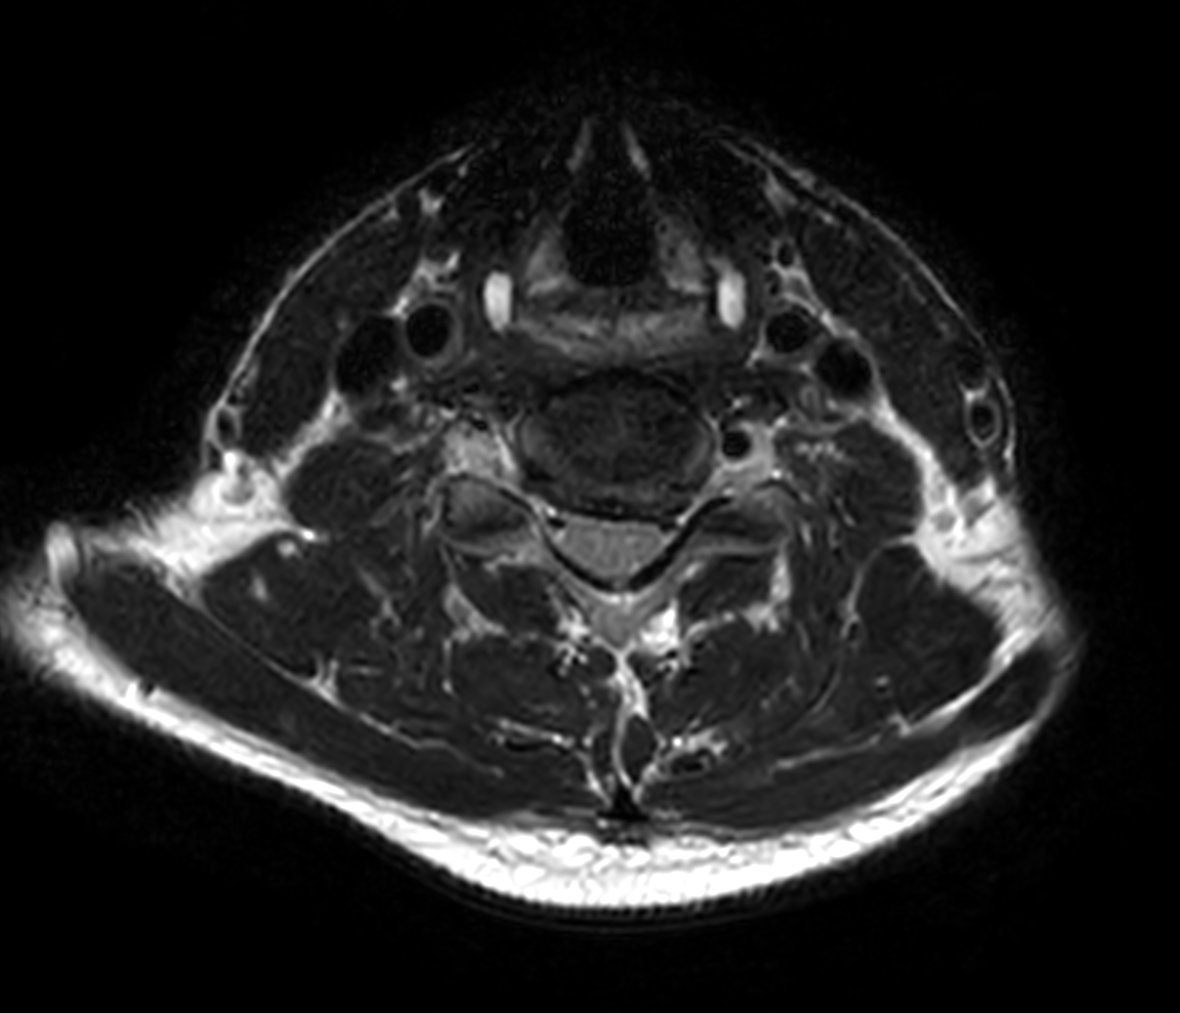

Axial T1w TSE

Axial T1w TSE - Compressed SENSE